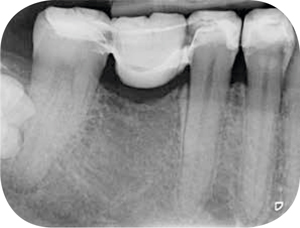

Afb. 9-10

Solo-opnamen van het 1e en 3e kwadrant.

Röntgenonderzoek

Röntgenologisch onderzoek laat meerdere problemen zien. Onder andere een forse zwarting apicaal van element 12 met het beeld passend bij periapicale problematiek en een verleden van apicale chirurgie (afbeelding 8-12 ).